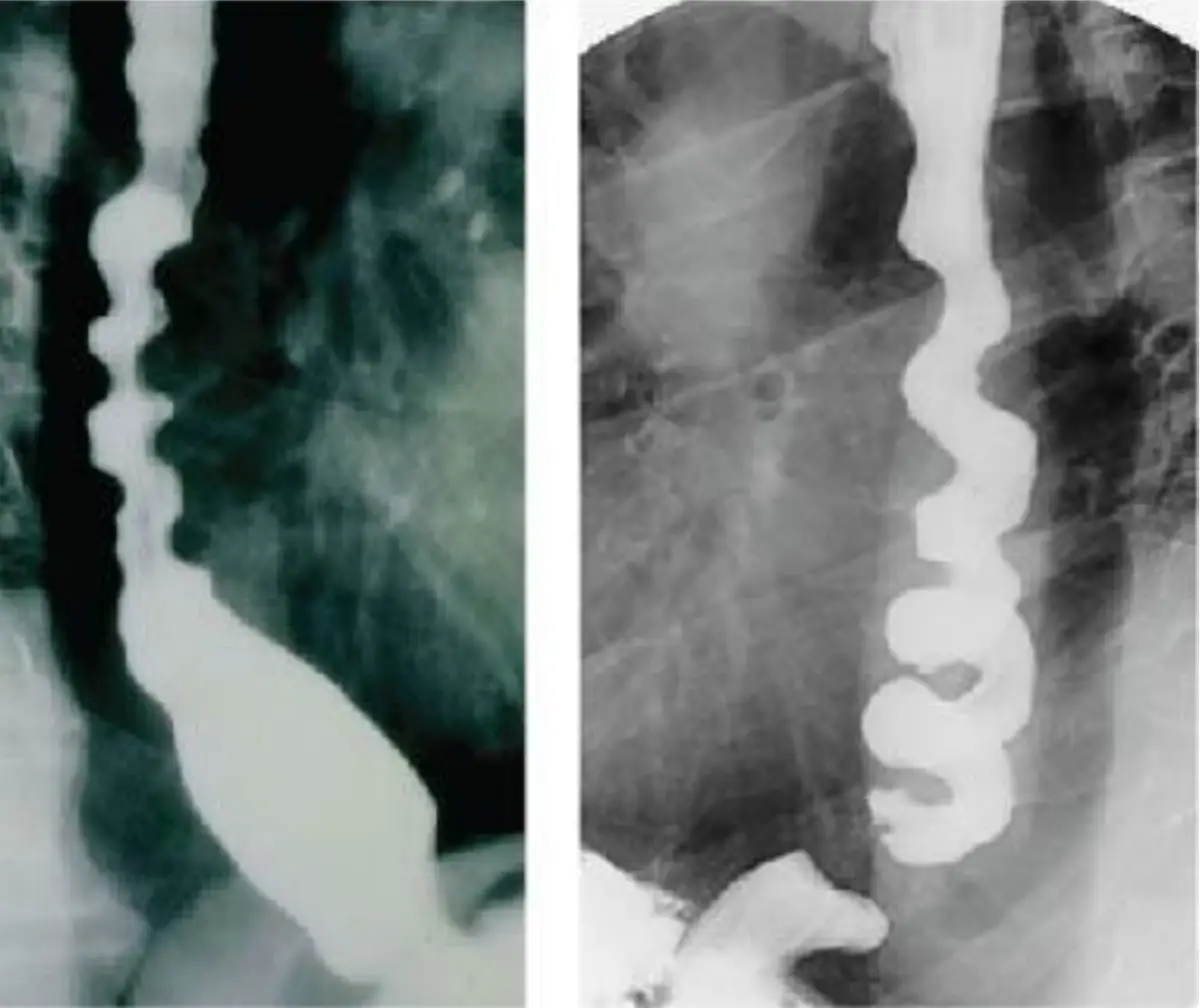

本題主軸在於食道動力障礙的鑑別:圖A呈現食道近端擴張伴下括約肌呈尖狀(bird’s-beak)狹窄,是典型的achalasia;圖B呈現多處非協調性收縮,形似rosary-beads或corkscrew,是diffuse esophageal spasm(DES)。

圖B(左側):食道中下段多處不規則、節段狹窄與擴張交錯,像念珠(rosary-beads)或肉串(shish-kebab);食道呈「corkscrew」狀,顯示非協調性收縮,符合DES。

圖B(右側):同一節段在動態造影中多發性收縮與鬆弛交替,進一步印證spastic性運動障礙。